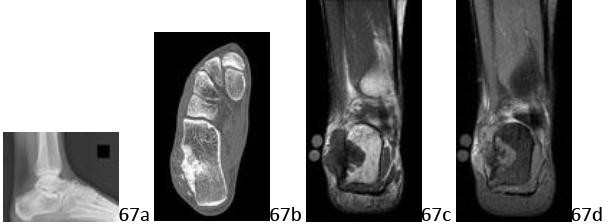

3. # 67a 67b 67c 67d A 20-year-old woman has progressive severe heel pain, swelling, and difficulty with shoe wear. A mass has been present for several weeks, and the pain awakens her from sleep and requires narcotics for symptomatic control. Figures 67a through 67d show the lateral radiograph, CT scan, and coronal T1- and T2-weighted MRI scans, respectively. What is the most likely diagnosis?

1. # Enchondroma

DISCUSSION: The radiograph reveals a blastic-appearing lesion within the body of the calcaneus. The CT scan confirms the presence of a blastic lesion within the bone, and shows extension into the soft tissues with mineral density (bone formation) in the lateral aspect of the heel. The MRI scans confirm that the lesion extends outside the bone with a lobular-appearing soft-tissue mass with low T1-weighted and intermediate T2-weighted signal, both of which show the low signal intensity associated with bone formation. This is most characteristic of a bone-forming lesion that is behaving in an aggressive fashion, and represents an osteosarcoma of the calcaneus. Metastatic carcinoma is highly unlikely in this age and location, and would not generally present with mineral density in the soft tissue. Giant cell tumor, while it may extend outside the bone, is not a blastic lesion. Osteoblastoma, while blastic and expansile, does not generally present with soft-tissue invasion. This lesion does not have the appearance of an enchondroma, which would be contained within the bone (no soft-tissue extension) and demonstrate "rings and arcs" mineral density on imaging. The Preferred Response to Question # 67 is 3.